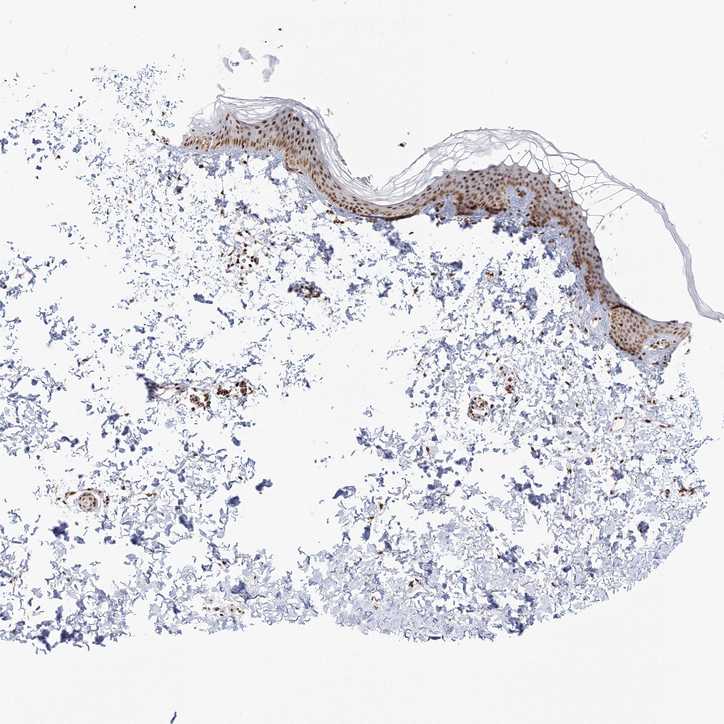

SKIN 1 - Antibody stainingi

Antibody staining in the annotated cell types in the current human tissue is reported as not detected, low, medium, or high, based on conventional immunohistochemistry profiling in selected tissues. This score is based on the combination of the staining intensity and fraction of stained cells.

Each image is clickable and will lead to virtual microscopy that enables deeper exploration of all samples and also displays staining intensity scores, fraction scores and subcellular localization as well as patient and tissue information for each sample.

Antibody HPA036909Antibody HPA036910

Langerhans LowMedium

Fibroblasts MediumHigh

Keratinocytes MediumHigh

Melanocytes HighHigh

SKIN 2 - Antibody stainingi

Epidermal cells HighHigh